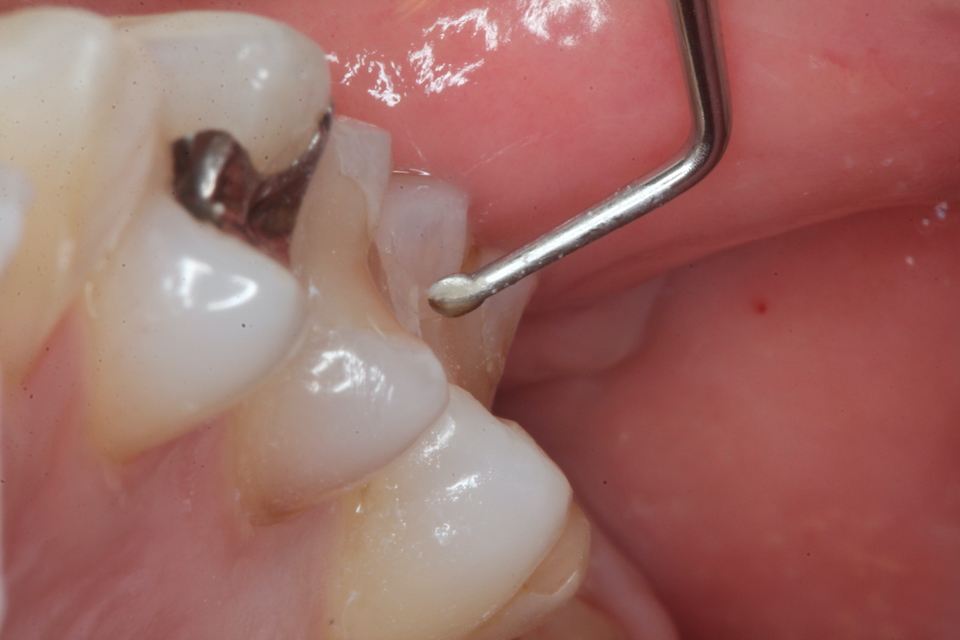

下顎7番の頬側歯茎部カリエスの原因 2025.06.04